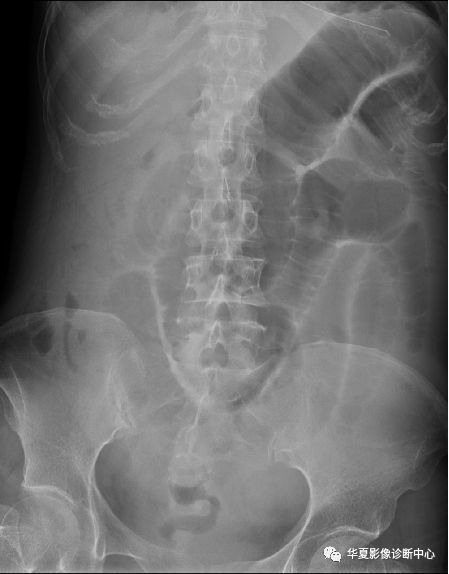

一文让你掌握,肠梗阻x线表现

肠梗阻平片

肠梗阻腹部平片